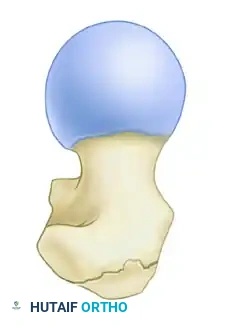

1. The Modified Medial Trochanteric Entry Portal

For the fixation of intertrochanteric femoral fractures, the selection of the entry portal is arguably the most critical step of the operation. We advocate for the modified medial trochanteric portal.

Anatomical Landmarks: The modified medial trochanteric portal is located on the medial aspect of the greater trochanter, directly along the trochanteric ridge on the AP view, and perfectly in line with the central axis of the femoral shaft on the lateral view.